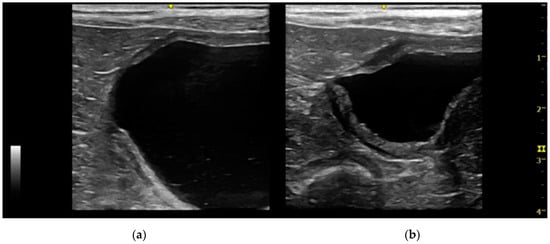

Patent urachus was present in only one mixed-breed dog of 6 months of age. The urachal presented a tubular structure and anechoic content. The formation began from the bladder and ended at the umbilicus (Figure 5).

Historically, the diagnosis of UA in veterinary medicine was performed by the use of different imaging techniques, such as ultrasonography, contrast cystography, and cystoscopy [3,14,23]. In previous studies, contrast cystography was used to diagnose UA [8,12]. According to Osborne and colleagues, positive antegrade cystourethrography and retrograde positive contrast urethrocystography were considered the procedures of choice for the diagnosis of vesicourachal diverticula [4]. In the present study the diagnosis of UA was based on abdominal ultrasonography only. Abdominal ultrasound has the advantages to be a routinely available and non-invasive imaging technique. Similarly, in human medicine, abdominal ultrasound is considered a fast and readily available technique to diagnose UA in absence of the risks connected to radiation exposure [7]. However, we should consider that the diagnostic power of abdominal ultrasonography in identifying UA may be reduced by a condition of inadequate bladder filling. In one of the patients of our study, the diagnosis of intramural vesicourachal diverticulum was made at the second ultrasonography, when the bladder appeared less filled (Figure 7). Therefore, we cannot exclude that small diverticula may be undiagnosed by the use of ultrasonography, in case of inadequate bladder filling.

Figure 5. Longitudinal ultrasound images of a patent urachus in a dog. A tubular structure (≤5 mm diameter) with a small amount of anechoic content extends from the cranio-ventral bladder wall to the umbilical region. Mild reactivity of the peritoneal fat and a small quantity of peritoneal fluid are present in proximity of the urachus. (a) Terminal urachus part reaching the umbilical region; (b) intermediate urachus part; (c) urachus part in continuity with the bladder apex.

Figure 7. Two longitudinal ultrasound images of the urinary bladder of a dog with an intramural vesicourachal diverticulum. The images show two different volumes of urine into the bladder lumen. (a) Overly distended: the diverticulum appears as a not very visible focal depression in the cranial-ventral aspect of the bladder, with thinning of the correspondent bladder wall; (b) ddequately distended: the diverticulum appears as an evident, focal, evagination in the cranio-ventral aspect of the bladder.